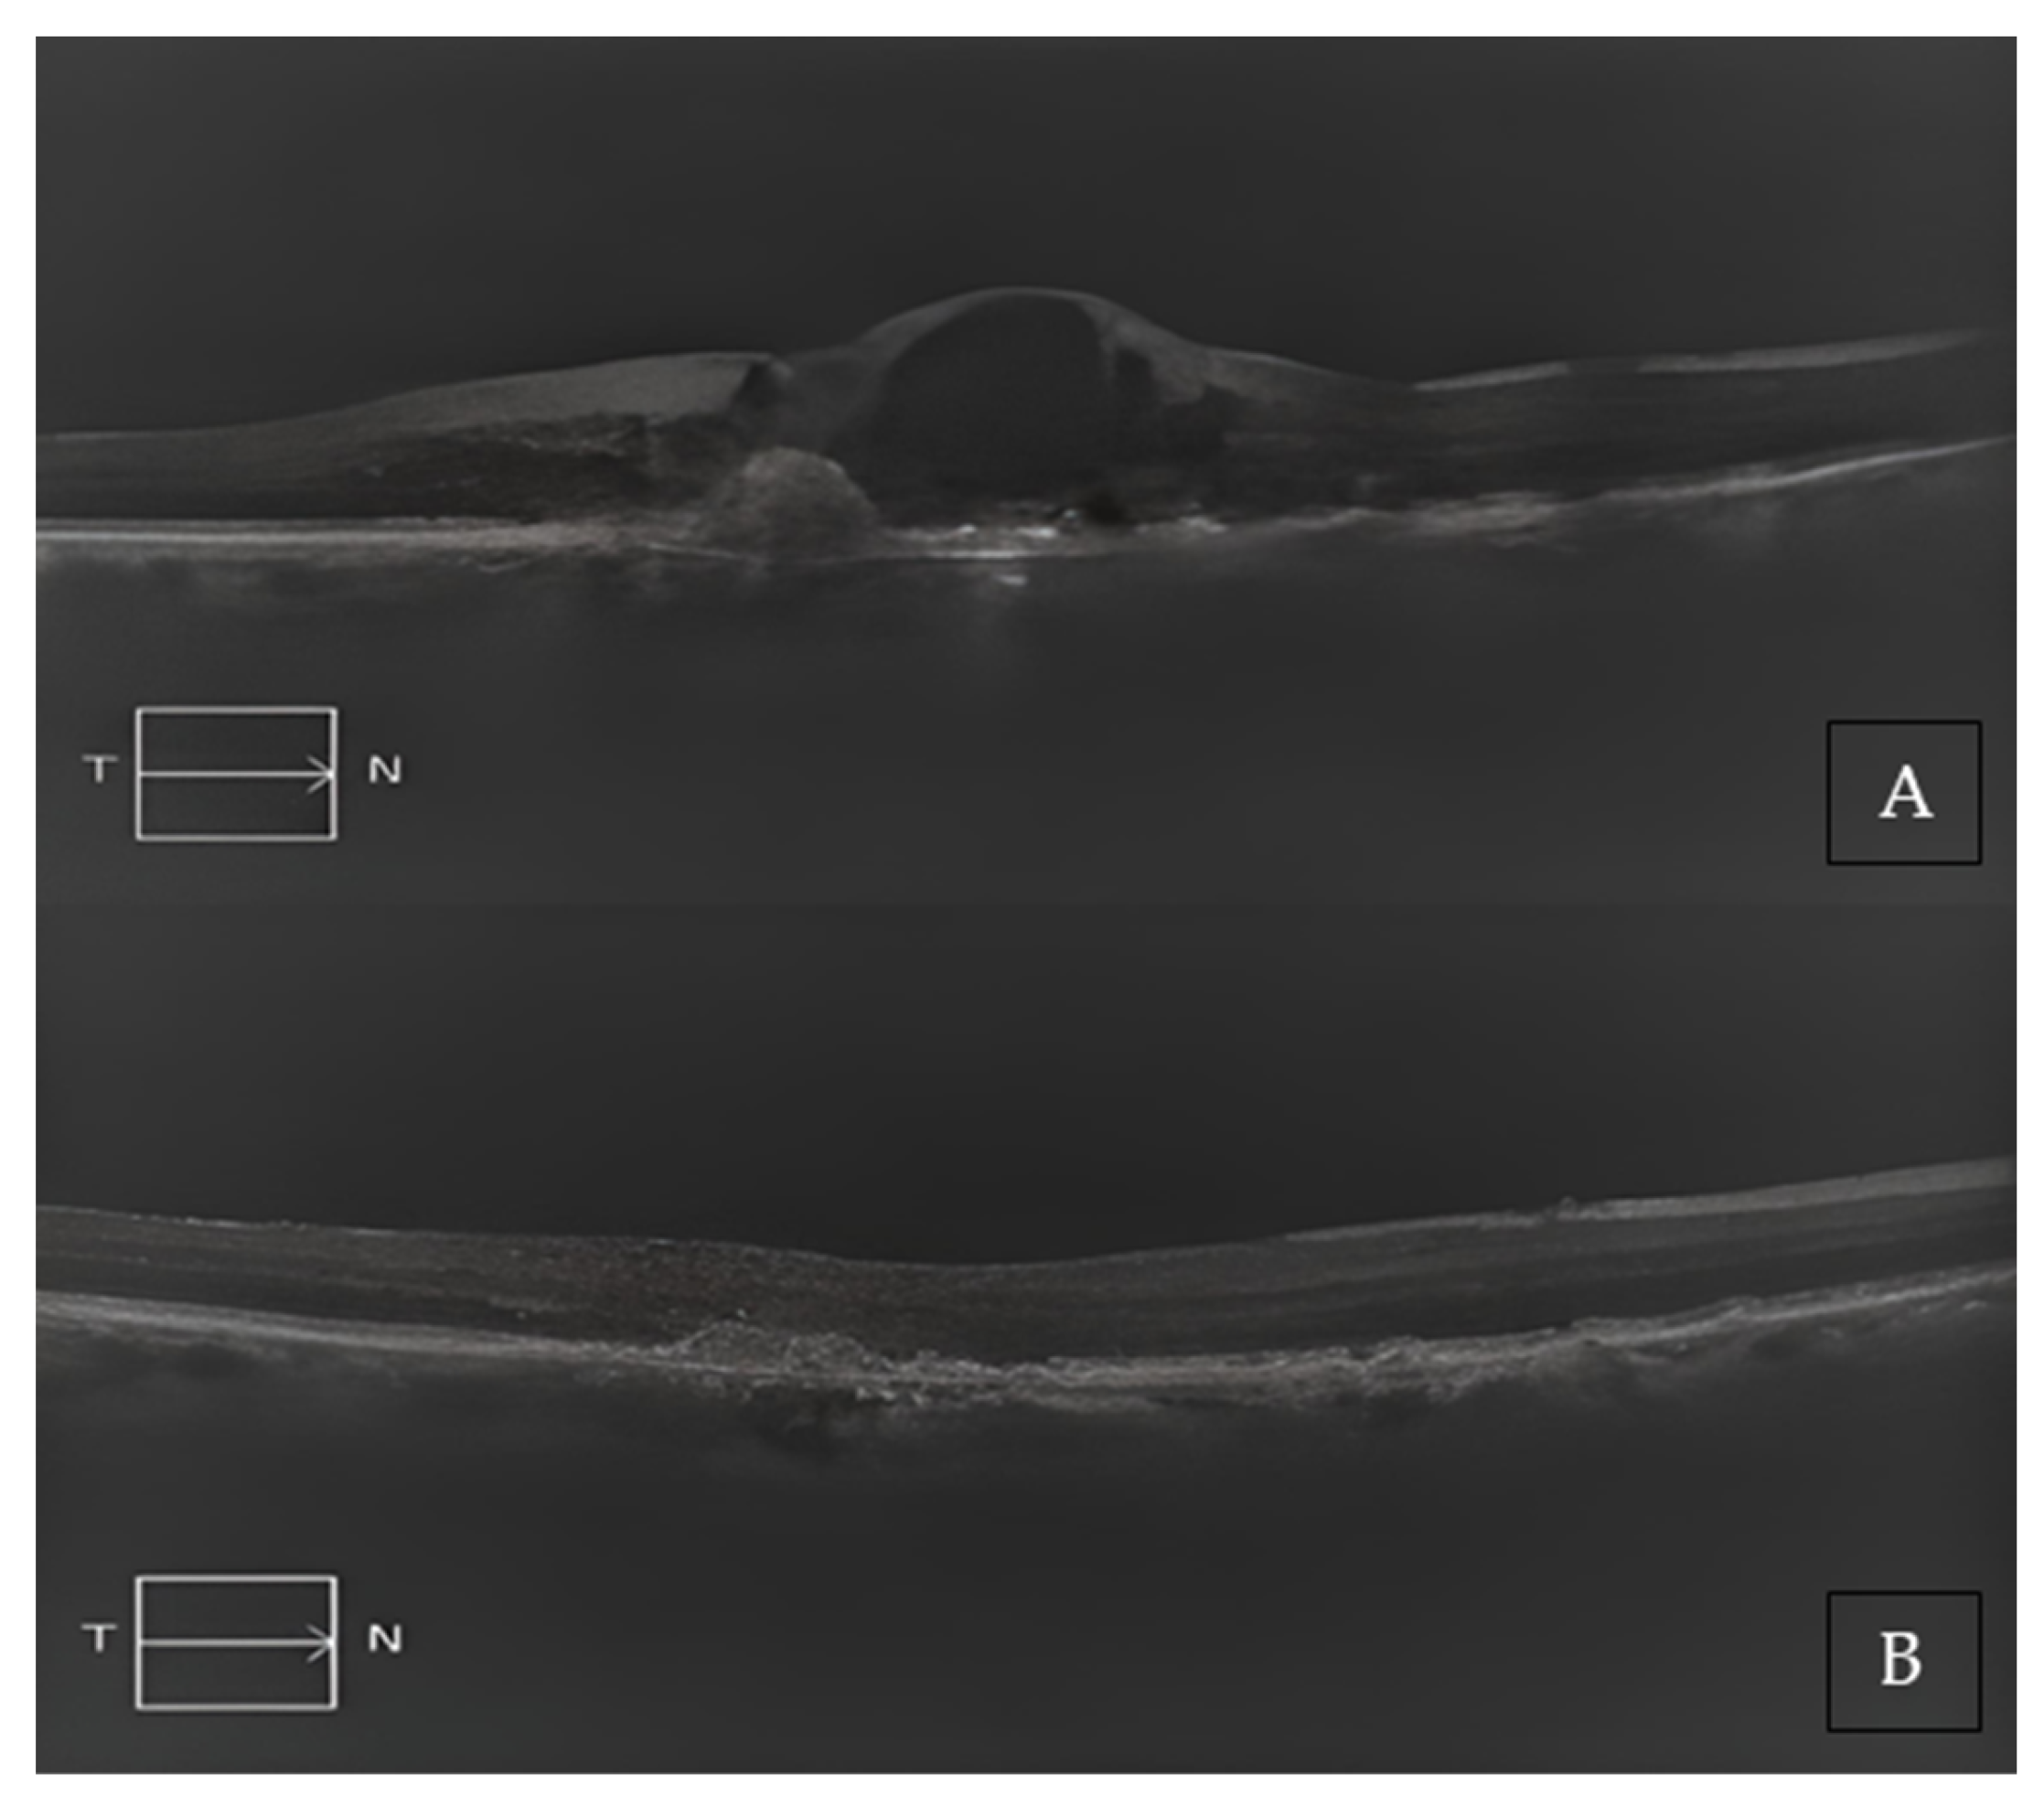

Two representative cases of patients from our cohort, before and after treatment with Brolucizumab, are shown in Figure 2A,B and Figure 3A,B.

Figure 2. (A) Baseline SD-OCT scan acquired with Maestro 3D OCT-1 (Topcon Corporation, Tokyo, Japan) of a non-treatment-naïve patient displaying diffuse intraretinal edema. (B) A 4-month SD-OCT scan acquired with Maestro 3D OCT-1 (Topcon Corporation, Tokyo, Japan) displaying subretinal hyper-reflective material and no residual edema.